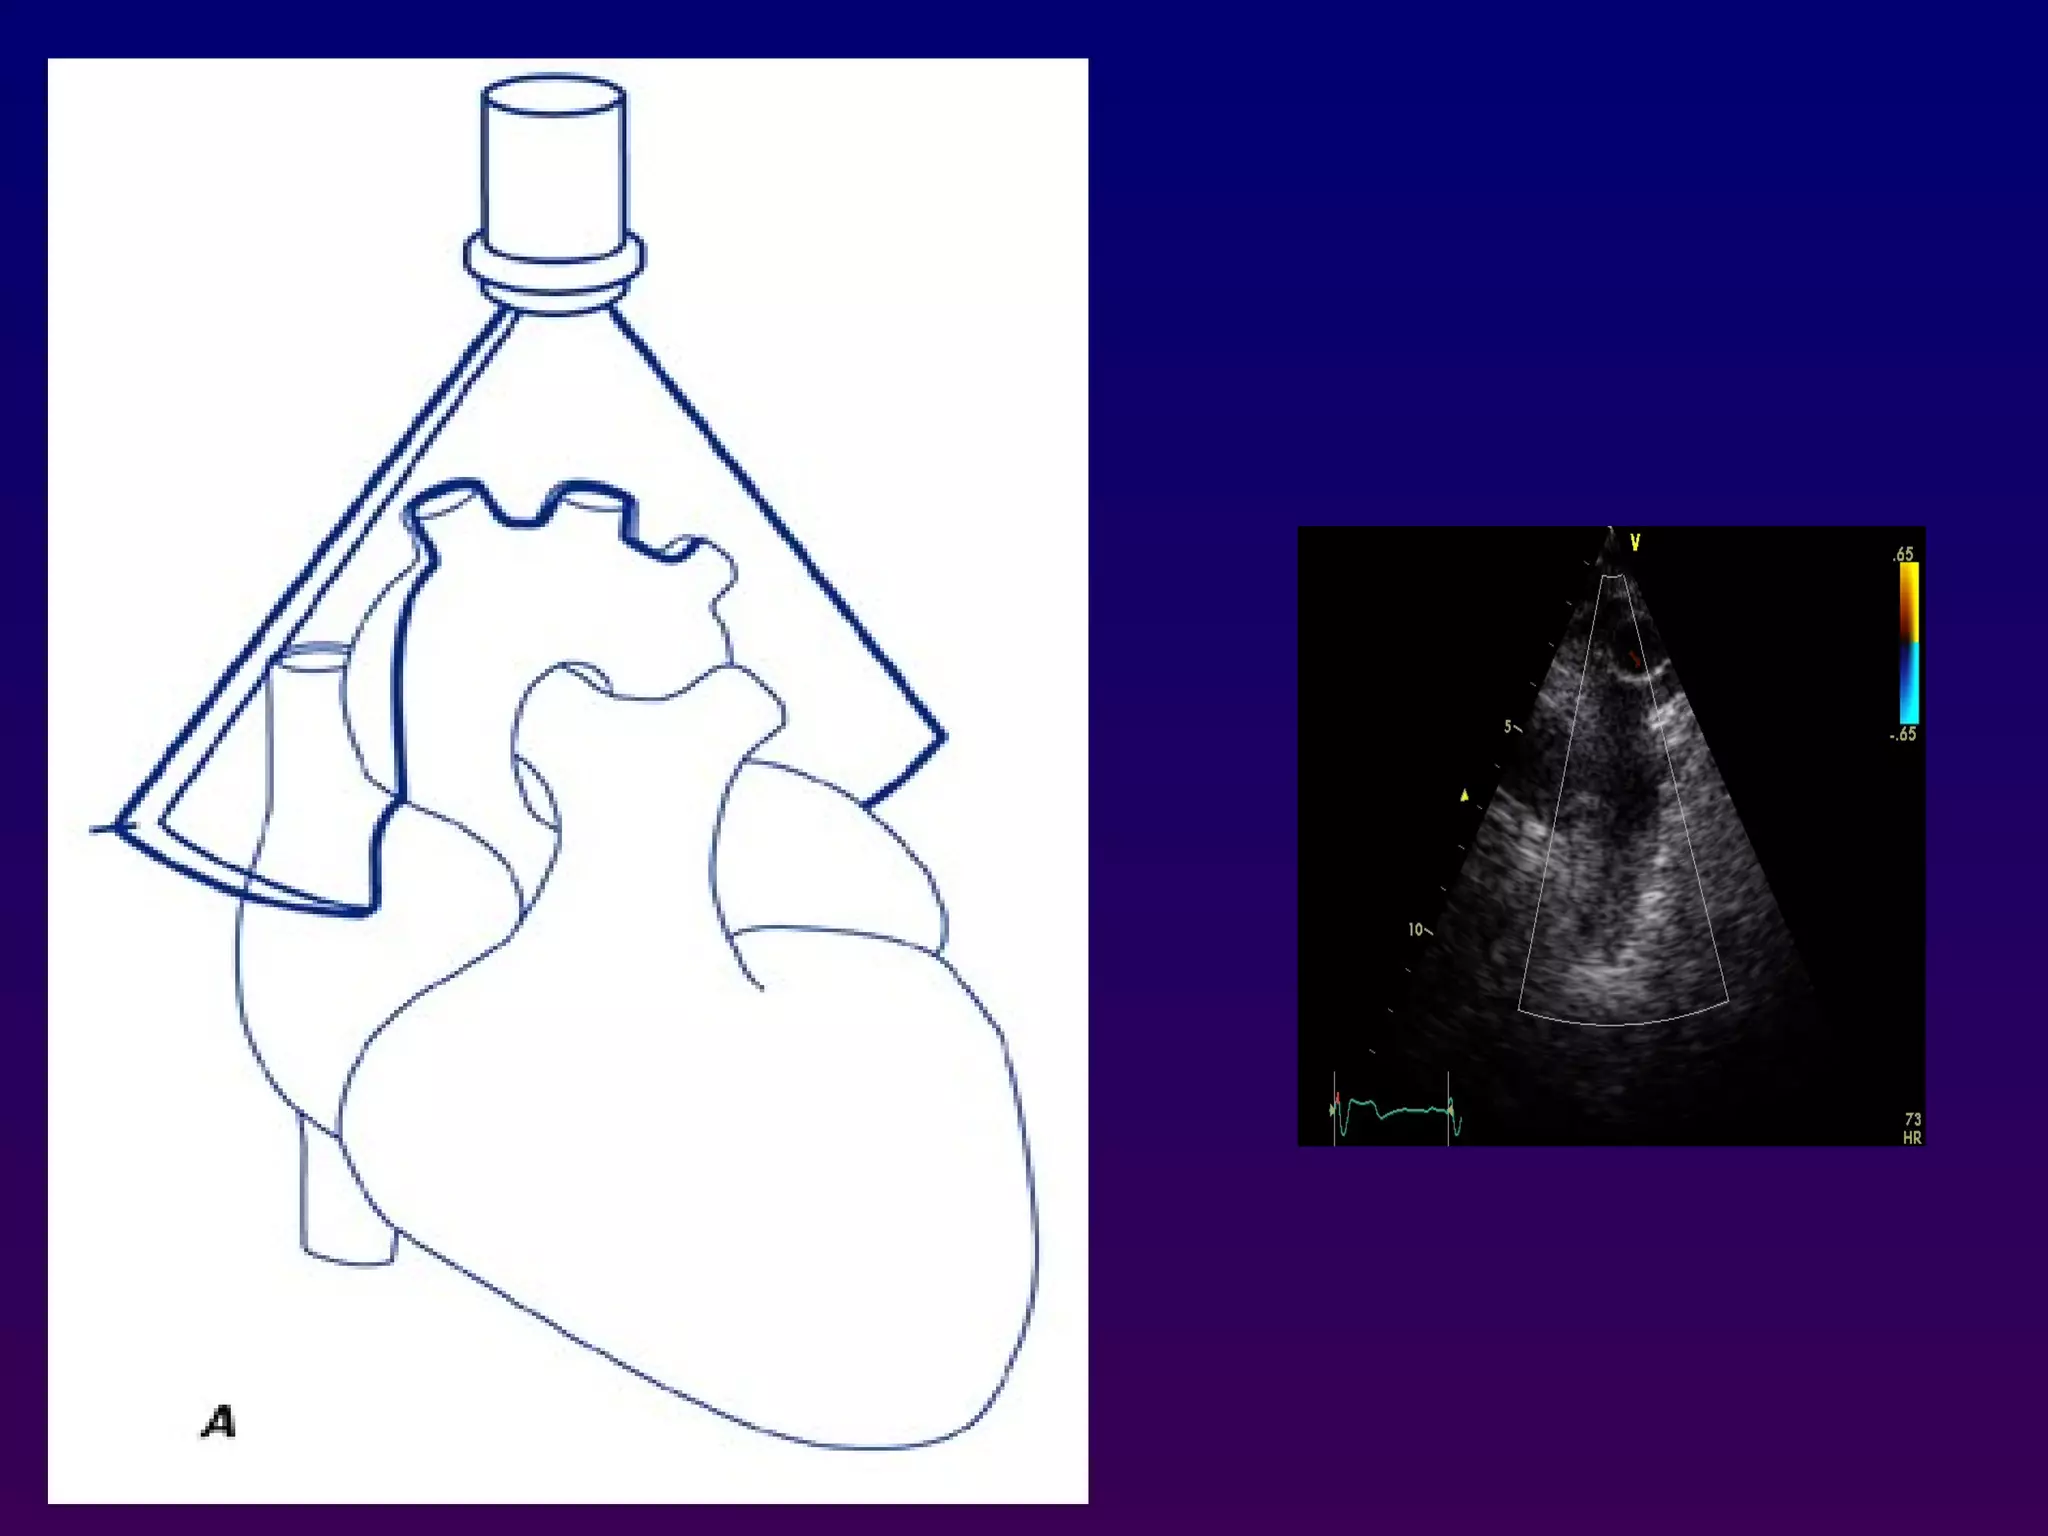

Subcostal four-chamber

The subcostal views may be obtained either with the

patient in supine position with the knees bent to

relax the abdominal musculature. The transducer is

positioned immediately below or to the right of the

xiphoid process. This allows visualization of the

basal, mid, and apical right ventricle, the inferior

interventricular septum, and anterolateral left

ventricular walls. The interatrial septum is oriented

nearly perpendicular to the ultrasound beam.

Subcostal four-chamber The subcostalviews may be obtained either with the patient in supine position with the knees bent to relax the abdominal musculature. The transducer is positioned immediately below or to the right of the xiphoid process. This allows visualization of the basal, mid, and apical right ventricle, the inferior interventricular septum, and anterolateral left ventricular walls. The interatrial septum is oriented nearly perpendicular to the ultrasound beam.